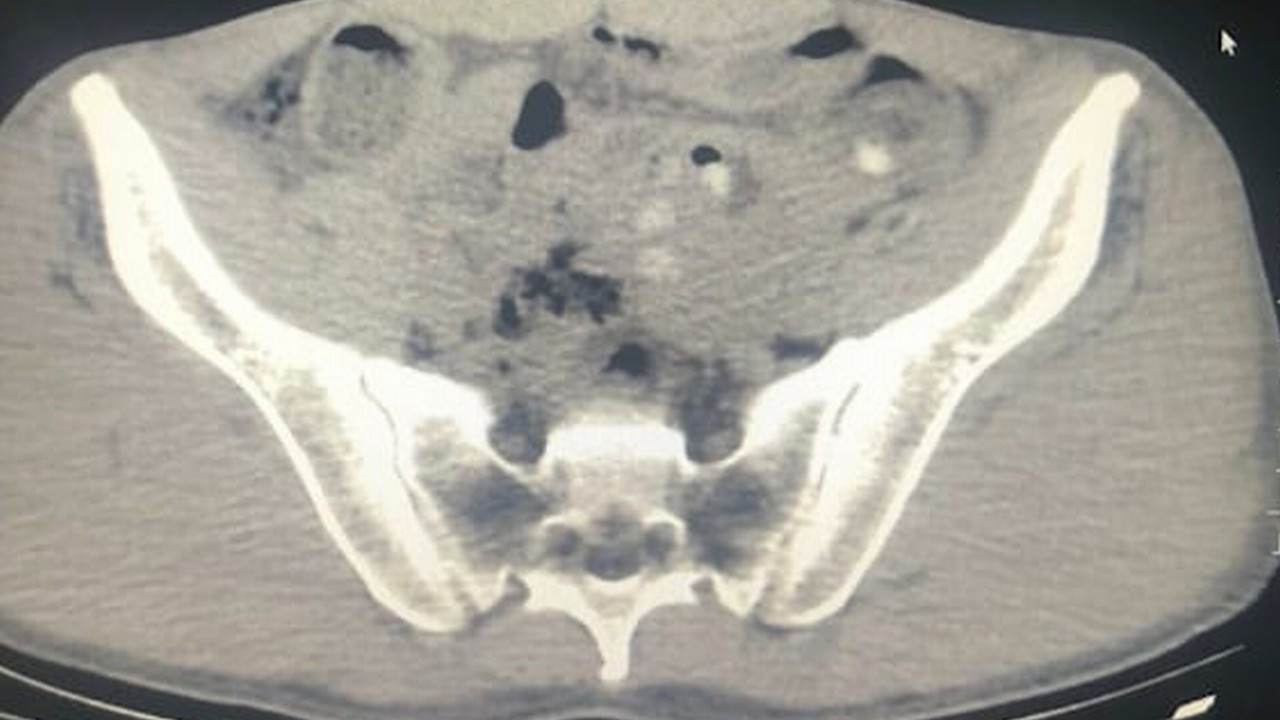

Gözaltına alınıp hastaneye götürülün şüphelilerin çekilen röntgenlerinde de midelerinde 45 kapsül metamfetamin tespit edildi.

Şüphelilerin midesindeki uyuşturucu doğal yollarla çıkarıldı.